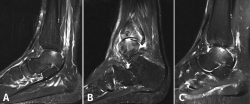

Las clasificaciones de las LOC se basan principalmente en sus características radiográficas. El sistema original de clasificación radiográfica fue desarrollado en 1959 por Berndt y Harty, y basado en proyecciones simples; posteriormente, Loomer añadió el grado V (Tabla 1)(16,17). Antes de esta adición, la clasificación de Berndt y Harty solo abordaba lesiones agudas o fracturas osteocondrales (grados I-IV), mientras que el tipo V (lesión quística) es más característico de las lesiones crónicas (Figura 1).

Figura 1. Radiografía que muestra una lesión osteocondral en la zona medial de la cúpula articular.

Otras clasificaciones están basadas en la tomografía axial computarizada (TAC) o en la resonancia magnética (RM) y engloban las LOC tanto agudas como crónicas. El estudio mediante TAC permite más precisión para definir el tamaño y la localización de las lesiones, así como de la presencia de cambios quísticos. Ferkel y Sgaglione desarrollaron un sistema de clasificación basado en la TAC (Figura 2), que tiene la particularidad de servir de apoyo para la planificación preoperatoria y la elección del tipo de tratamiento más adecuado (tornillo/pin, microfractura o injerto)(18).

Figura 2. Imágenes de resonancia magnética que muestran diferentes fases de lesión osteocondral. A: estadio IIA, que muestra edema óseo circundante; B: fractura osteocondral en estadio IV con un fragmento desprendido y desplazado; C: estadio V que muestra la formación de quistes subcondrales.

Hepple desarrolló un sistema de clasificación basado en la RM y que también tiene implicaciones de indicación (Tabla 2). Actualmente, la RM constituye el mejor método para evaluar la estabilidad de un fragmento mínimamente o no desplazado, lo que puede influir en la necesidad, o no, de practicar su fijación (Figura 3)(19,20).

Figura 3. Imagen de tomografía axial computarizada de un estadio III que muestra un fragmento no desplazado con lucencia por debajo.